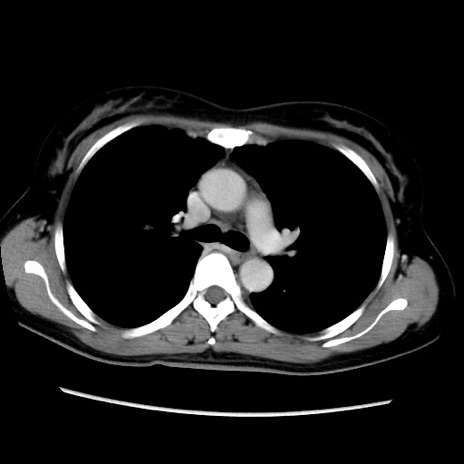

MRI(4日後)

【症例】40歳代女性

【主訴】上下腹部痛

【現病歴】2日目から下腹部痛あり。夜間は痛みで眠れなかった。昨日より上腹部痛と下痢が出現。臥位で痛みは軽快したため、休んでいた。本日になって臥位でも立位でも痛みが強くなってきたため救急要請。

【既往歴】子宮内膜症

【身体所見】部:平坦・軟、左上下腹部に圧痛あり、反跳痛あり。

【データ】WBC 21800、CRP 26.78